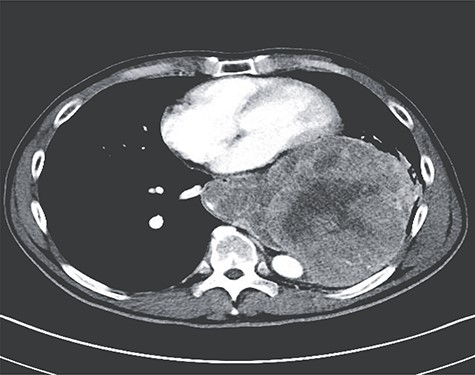

Imaging revealed tumor dimensions of 15–18 cm in diameter (Fig. 1). Following endoscopic ultrasound and positron emission tomography scan, a multidisciplinary board recommended surgical resection with esophagectomy through a thoracoabdominal incision. He was placed in a semirecumbent position. The costal margin was divided. The diaphragm was divided in a circumferential fashion leaving a rim of diaphragm on the chest wall. Gastric preparation was performed first (Fig. 2). Then, dissection was carried out along the mass into the chest. The mass was adherent to the pericardium and aorta but was encapsulated and not invading those structures. Multiple large aortoesophageal vessels were divided with the Ligasure vessel sealer device (Medtronic MN, etc.). The left lower lobe and inferior pulmonary vein were splayed across the mass. Inadvertent injury of a branch of the inferior pulmonary vein required vascular repair. The mass emanated from the lower one-third of the esophagus (Fig. 3). The esophagus was divided at the level of the left inferior pulmonary vein and the mass removed. Frozen sections of the esophagus, surrounding pleural, pericardium and lung, were performed and were negative. The anastomosis was performed in a typical fashion with a circular end-to-end stapler. The diaphragm was reapproximated, and the extra conduit length was tacked down into the abdomen. The immediate postoperative course was largely uneventful, with negative radiographic leak test performed on postoperative Day 5 and the patient discharged to home on postoperative Day 7.

Axial image from preoperative CT of the chest demonstrating extension from esophagus and relation to the pericardium and thoracic aorta.